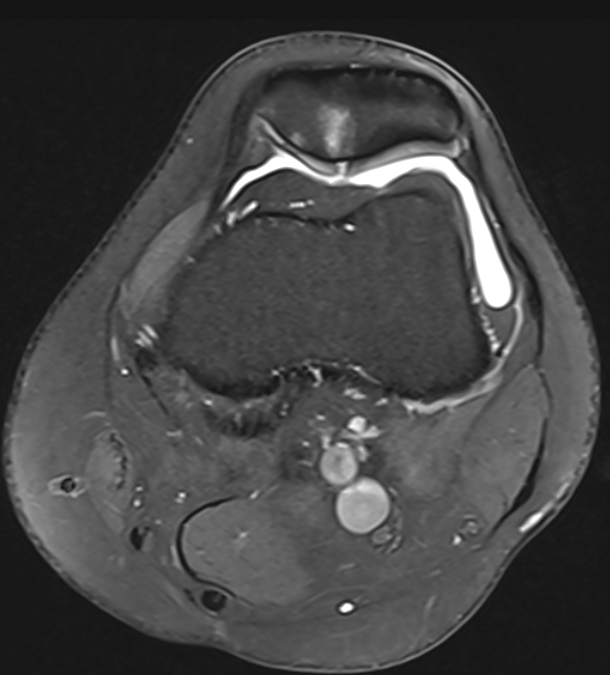

3. Cartilage fissure at patellar apex